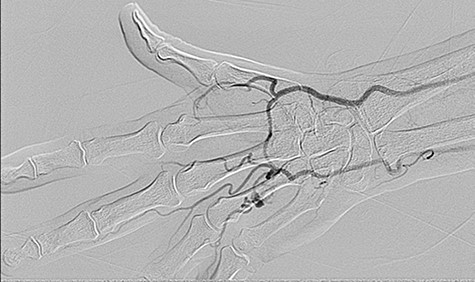

On examination, there was a pulsatile, firm swelling on the ulnar aspect of the right palm with no tissue loss. There was a palpable radial pulse, but no ulnar pulse found on clinical examination. Doppler signals over the digital arteries, ulnar and radial artery were detected. The patient was asymptomatic, and capillary refill time was normal. An initial ultrasound scan demonstrated a 17 × 8 × 13 mm aneurysm of mixed echogenicity in the palmar arch. This was further characterized through angiography (Fig. 1) and was confirmed to be in fact an aneurysm of the common digital artery in the fourth web space.

Angiogram showing aneurysm of the common palmar digital artery in the fourth web space.